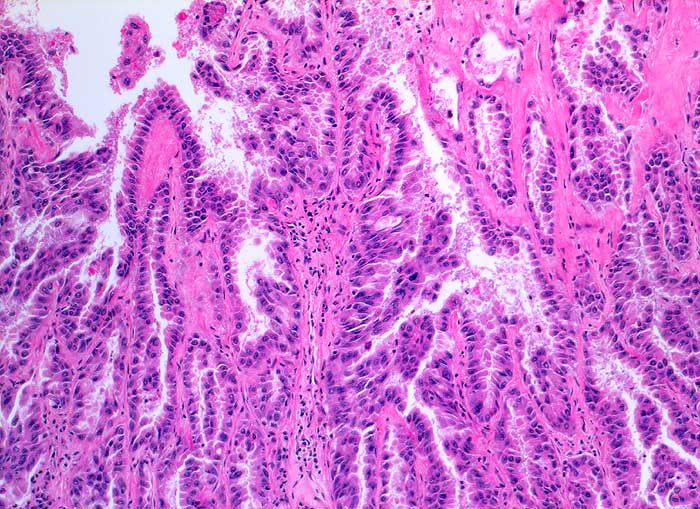

Adenokarzinom der Lunge

Papilläre und tubuläre Strukturen ausgekleidet von atypischem hochprismatischem Epithel entsprechend einem hochdifferenzierten Adenokarzinom.

Histologie

100